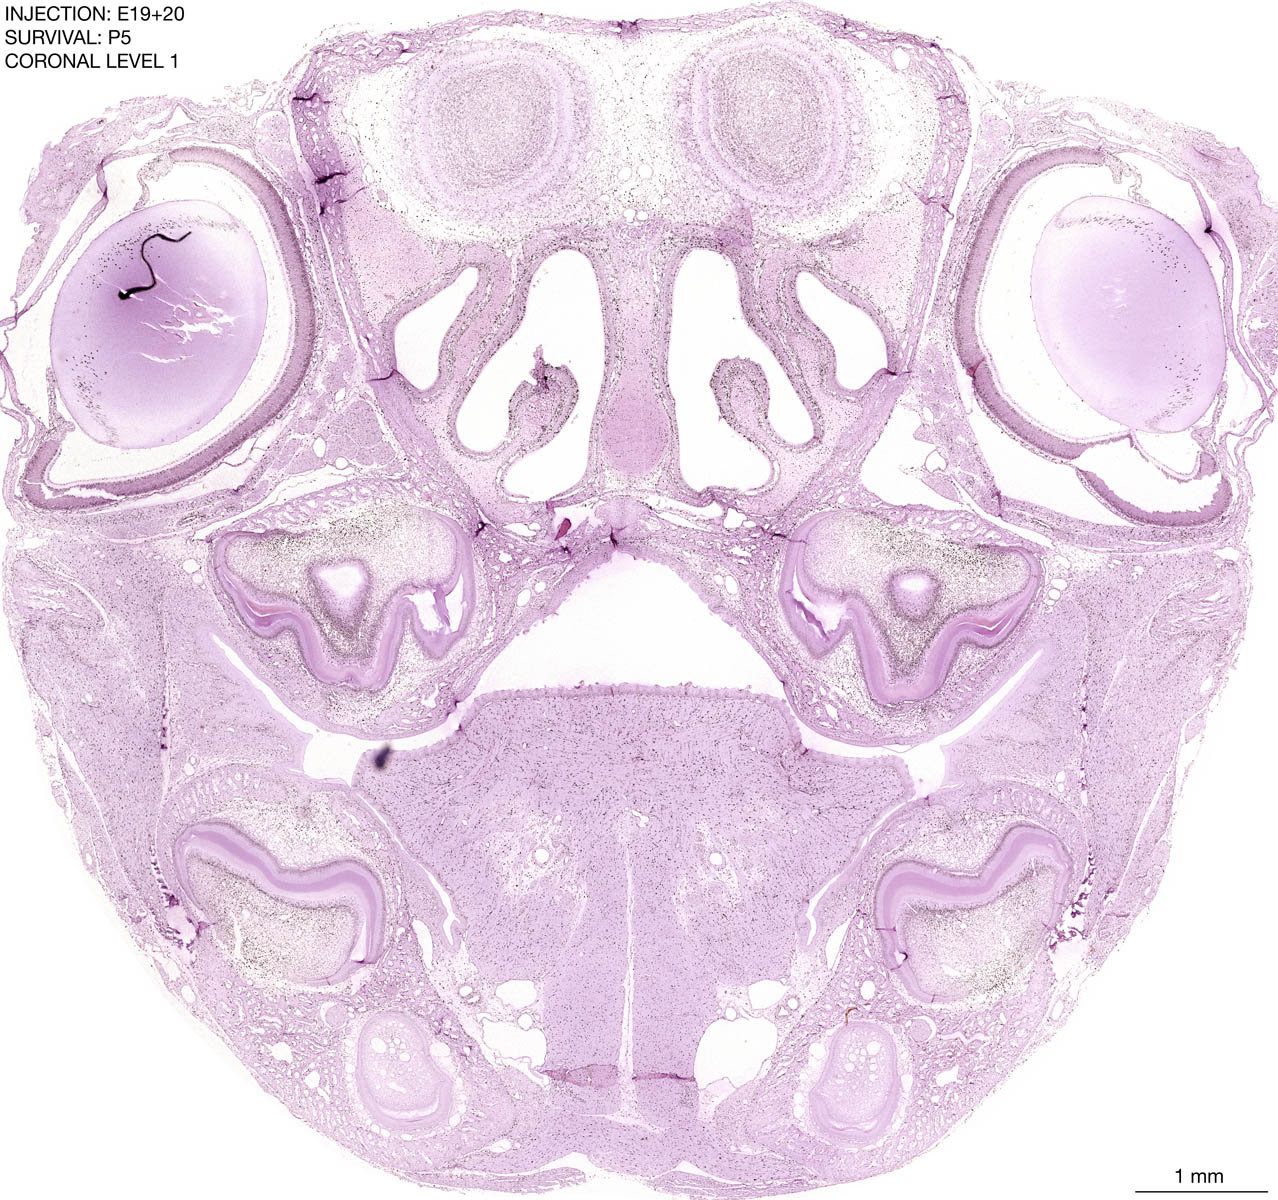

E19+20 P5 Survival The images below are from the brain of a rat that was exposed to tritiated thymidine on E19+20 and survived to P5. Download: Large | High Res Download: Large | High Res Download: Large | High Res Download: Large | High Res Download: Large | High Res Download: Large | High Res Download: Large | High Res Download: Large | High Res Download: Large | High Res Download: Large | High Res Download: Large | High Res Download: Large | High Res Download: Large | High Res Download: Large | High Res Download: Large | High Res Download: Large | High Res Download: Large | High Res Download: Large | High Res Download: Large | High Res Download: Large | High Res Download: Large | High Res Download: Large | High Res Download: Large | High Res Download: Large | High Res Download: Large | High Res Download: Large | High Res Download: Large | High Res Download: Large | High Res